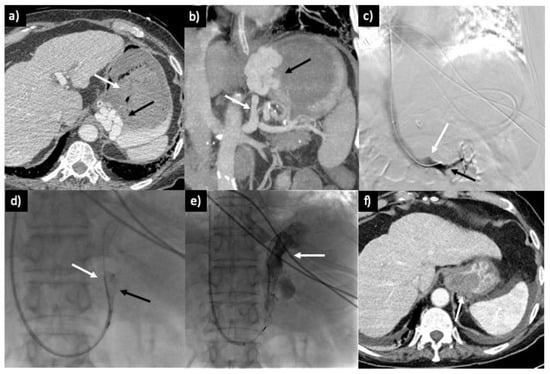

3.2. Technique

3.2.1. PARTO